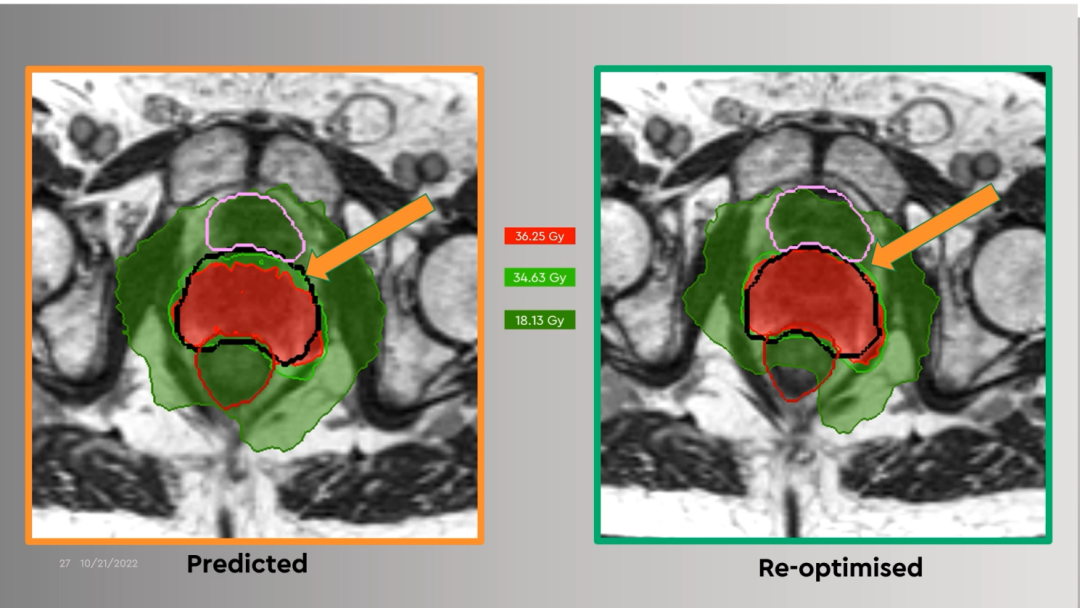

前列腺癌放疗时若使用原计划的剂量分布,会有较大欠量区,可以通过MRIdian在线自适应优化模块方便地改善欠量。

Figure 16前列腺癌放疗时若使用原计划的剂量分布,有较大欠量区(左);在线优化后的剂量分布,无欠量区(右)